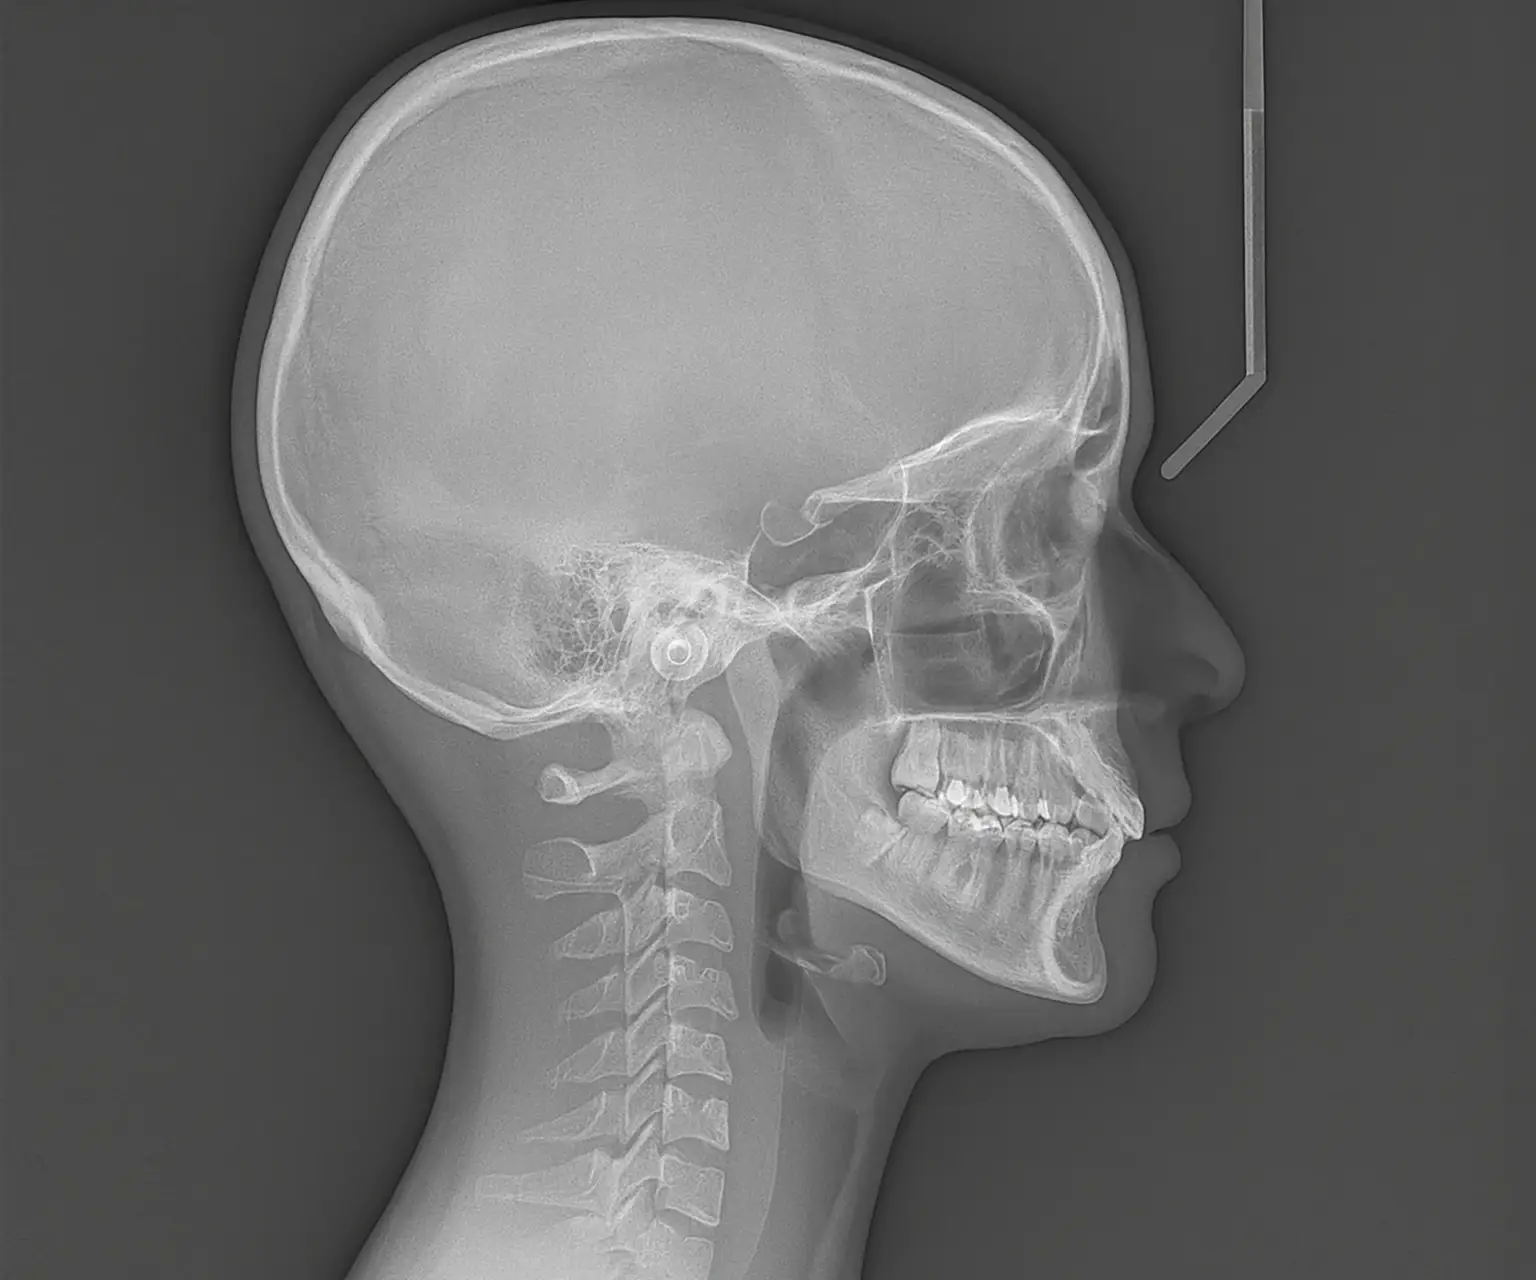

Kraniogram – pregled pozicije čeljusti i lica

Kraniogram je rendgenski prikaz glave i lica koji se koristi za analizu odnosa između gornje i donje čeljusti, osobito u ortodontskoj dijagnostici. Ova metoda omogućuje precizno planiranje terapije kod pacijenata koji imaju ortodontske ili funkcionalne poremećaje čeljusti.